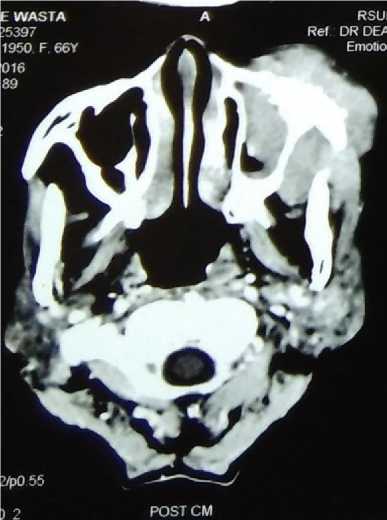

The skull X-ray was obtained, which showed the left maxillofacial bone became more blastic and thinner. We proceeded with contrast-enhanced CT scan which revealed solid mass at the left maxillofacial bone which infiltrating to left facial-buccal area, left maxillary sinus and left orbit, with bone destruction (Figure 1 and Figure 2). There was no infiltration to the intracranial area. There was no extranodal involvement of the lung, pleura, and liver.

Figure 1. Head CT axial view.